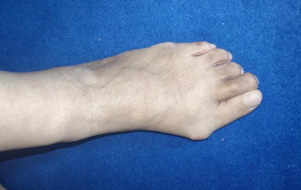

患者王阿姨因左足第2跖趾关节痛疼、活动不利30余年入院治疗。

近几年来,王阿姨左足第2跖趾关节痛疼症状加重,中药外洗、封闭治疗刚开始能暂时缓解疼痛。后来疼痛逐渐加重,已经严重影响到日常生活,实在因为疼痛难忍、肿胀、致无法行走,王阿姨这才在家人的陪伴下来到betway在线登陆就诊。

通过对王阿姨详细检查后,其被诊断为左足第二跖骨坏死、拇外翻伴有拇囊炎。石荣剑副院长手术团队根据病情,进行综合评估,决定保住阿姨的跖趾关节活动度。因此,石荣剑副院长与徐明亮主任手术团队为王阿姨定制了一套“个性化”的手术方案——第二跖趾关节置换术、拇外翻矫形术。